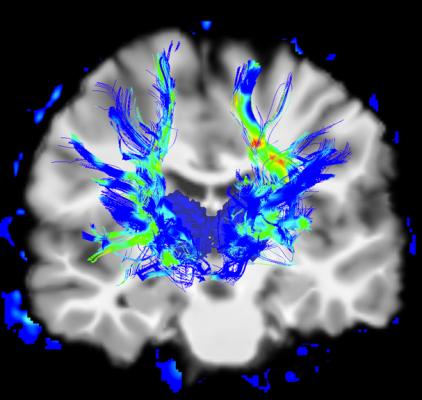

They used MRI data from 86 patients with mild Parkinson’s disease and 60 healthy control participants to generate the connectome, a structural/functional map of the brain’s neural connections. The researchers used the connectome to develop an index of disease exposure.

“In the present study, brain connectome, both structural and functional, showed the potential to predict progression of gray matter alteration in patients with mild Parkinson’s disease,” said study coauthor Federica Agosta, M.D., Ph.D., associate professor of neurology at the Neuroimaging Research Unit of IRCCS San Raffaele Scientific Institute in Milan, Italy.